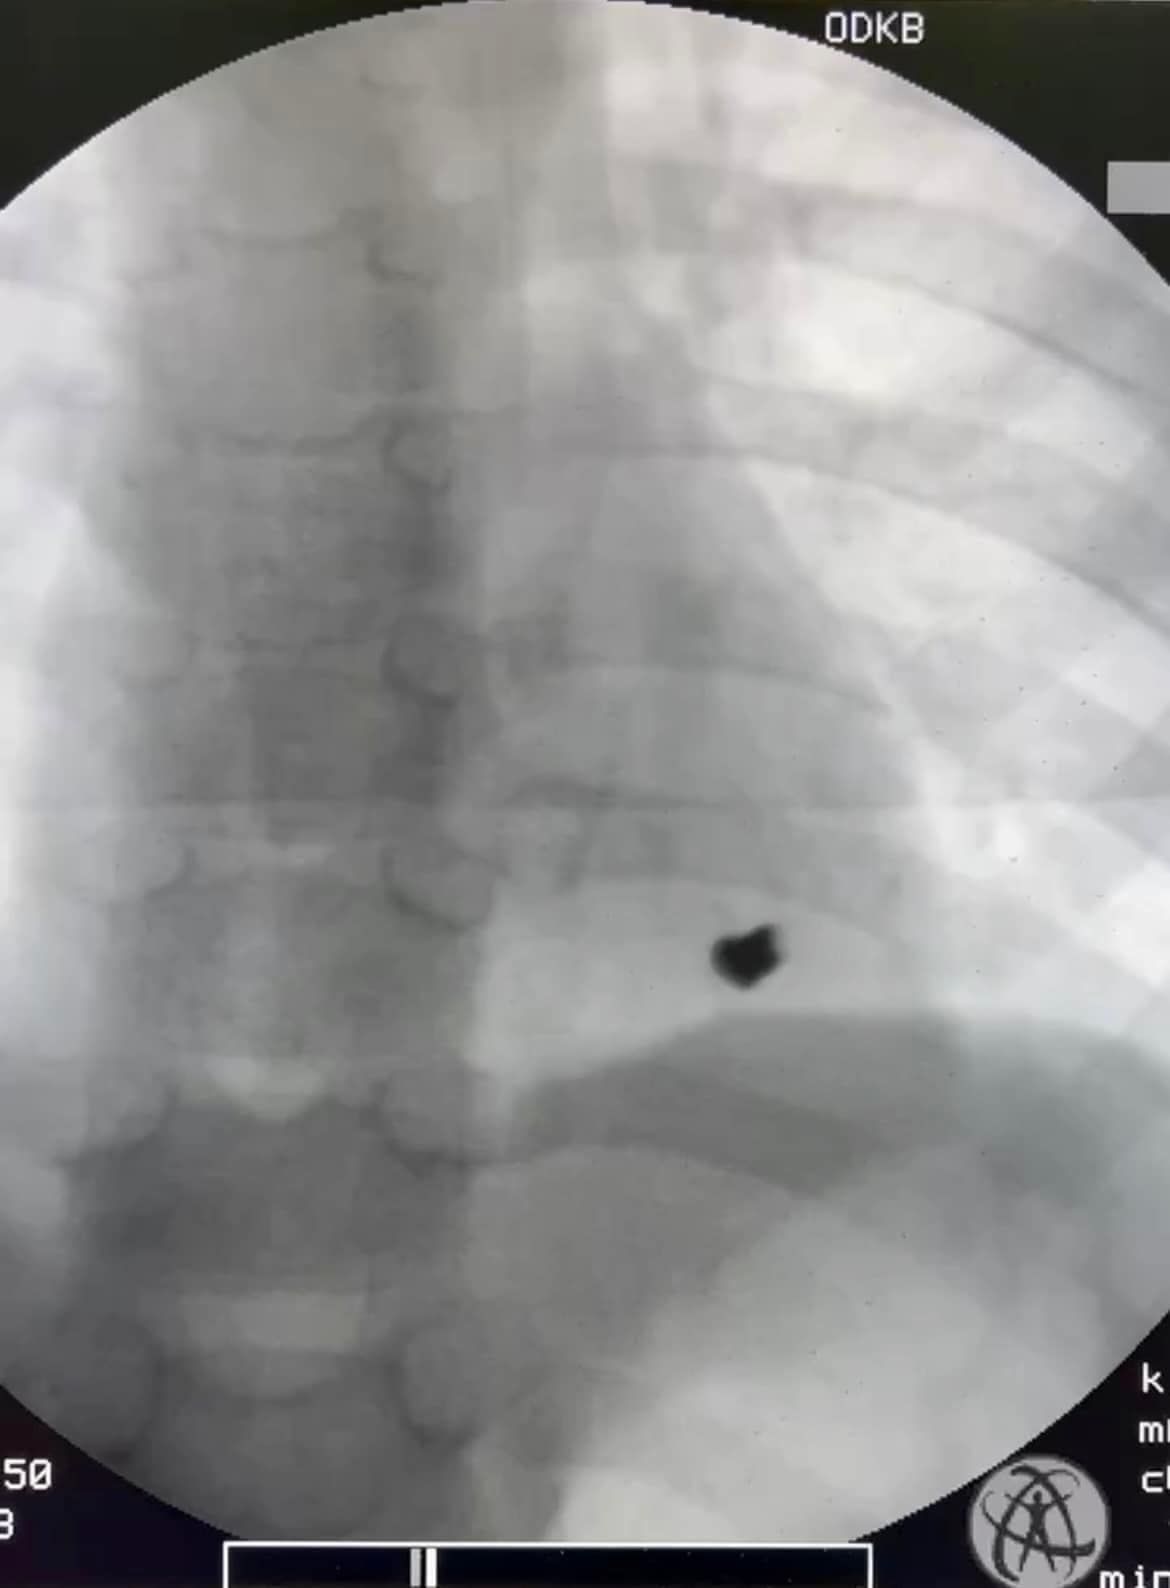

Гвинтівка, як виявилося, була заряджена. Трагедія сталася 1 квітня, і ця небезпечна гра закінчилася пораненням лівої частини грудної стінки з проникненням кулі в порожнину перикарду (серцевої сумки) та ураженням задньої стінки лівого шлуночка серця.

Куля потрапила в порожнину перикарду (серцевої сумки) та уразила задню стінку лівого шлуночка серця